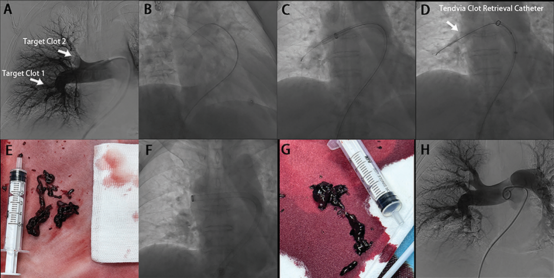

(Figure 4A)

The primary efficacy endpoint was the decrease in RV/LV diameter ratio from baseline to 48 hours postprocedure. The baseline RV/LV diameter ratio was 1.32 ± 0.31, whereas the RV/LV diameter ratio was 0.90 ± 0.17 at 48 hours postprocedure; the decrease in RV/LV diameter ratio was 0.42 ± 0.28 (95% CI: 0.37–0.47; P < 0.001), or 31.8%

图片

(Figure 4B)

The lower limit of the 95% CI (0.37) was above the set target value of 0.2, thus indicating that the device effectively decreased the RV/LV diameter ratio within 48 hours postprocedure. Moreover, it effectively removed clots and restored blood flow through the blocked pulmonary arteries, as demonstrated by computed tomography pulmonary angiography, and facilitated structural recovery of the right ventricle

(Figure 4C)

The secondary efficacy endpoint was the change in systolic PAP from pre- to postprocedure. The pre- and postprocedure systolic PAP values were 43.56 ±15.57 mmHg and 36.82 ± 14.23 mmHg, respectively, and the mean decrease in systolic PAP was 7.10 mmHg (16.3%; P < 0.001)